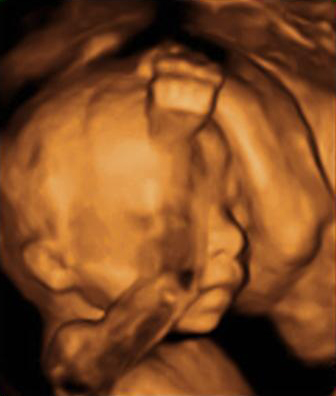

En la semana 20 de gestación el feto aún tiene mucho espacio para poder moverse. La embarazada notará esos movimientos, que se observan en la ecografía en 4D. Son las clásicas "pataditas" que nota la madre dentro del útero.

Ecografía: El bebé levanta los brazos

La ecografía capta al feto de 20 semanas de gestación en pleno movimiento ascendente.